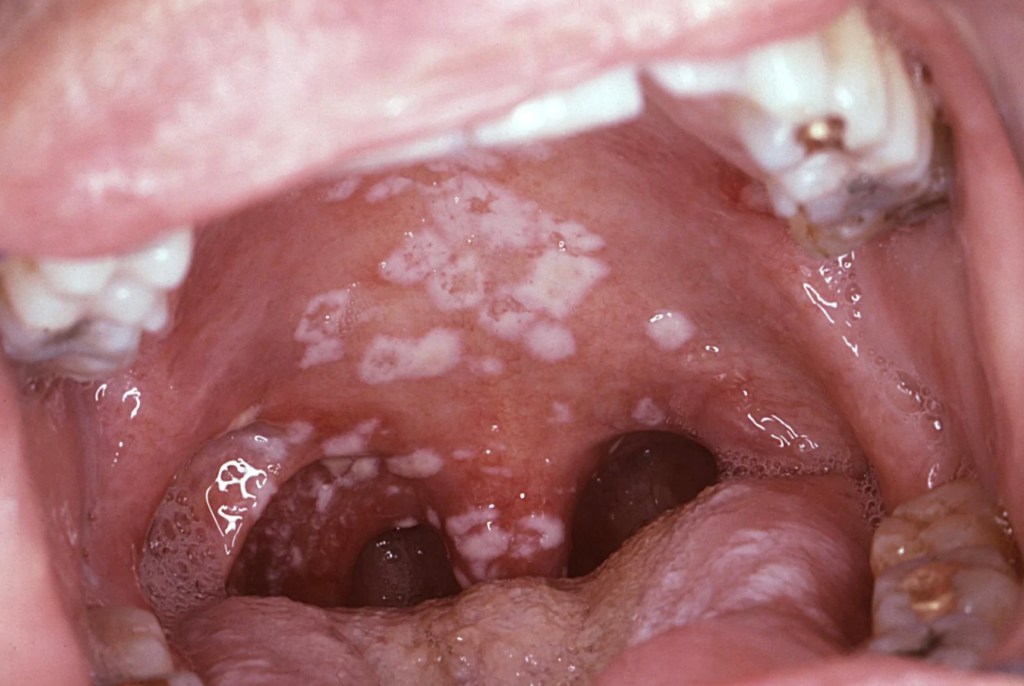

5.Oral thrush is causes by yeast like fungus called candida. This is also quite common. It is seen on those on broad spectrum antibiotics, diabetes, steroid therapy, immune compromising conditions including HIV infection. The white patches can easily be dislodged showing underlying erythema (redness) and inflammation. Anti-fungal lozenges will be very effective in its treatment along with treating the cause for the infection e.g., controlling the blood sugars and stopping the antibiotics.